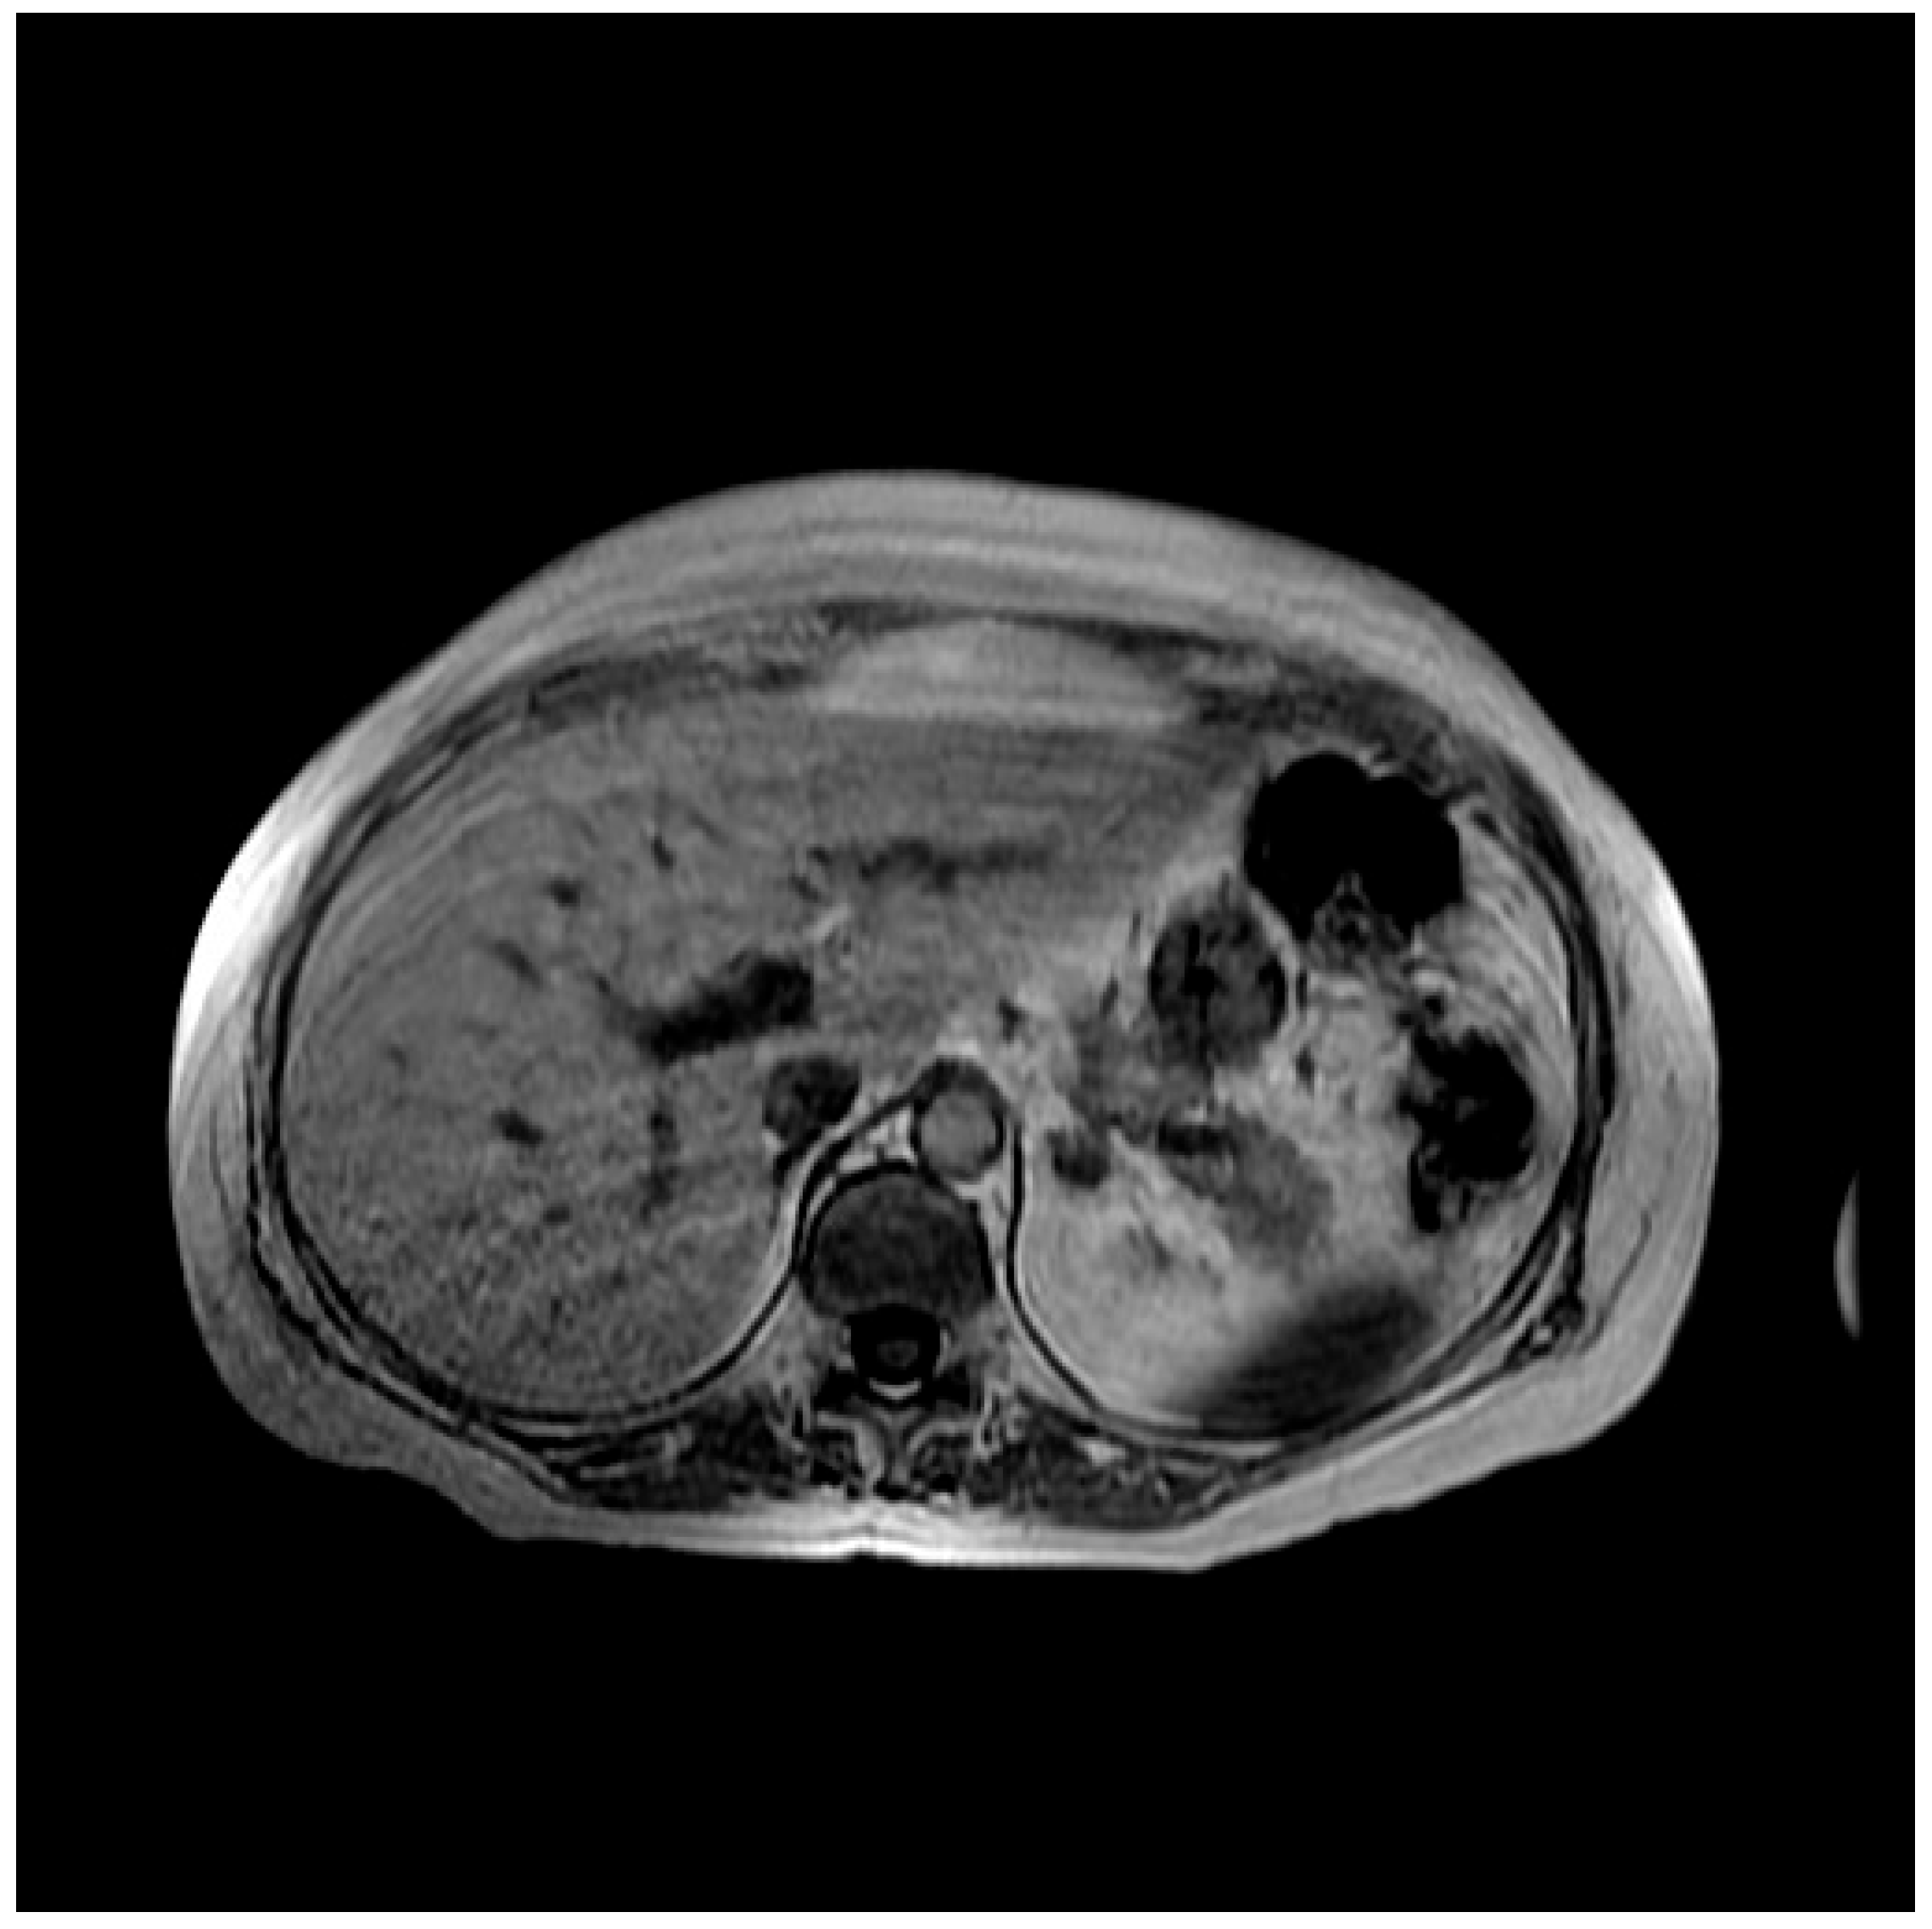

2. Case Presentation